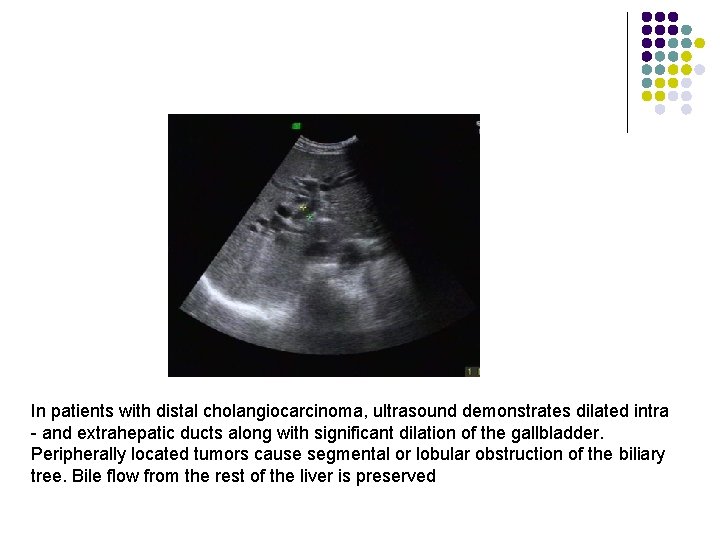

l l Peripheral cholangiocarcinoma may be suspected if abdominal ultrasound demonstrates local dilation of intrahepatic ducts or isolated dilation of the biliary tree inside one lobe of the liver. In both peripheral and hilar cholangiocarcinoma, biliary ducts distal to the obstruction (common hepatic duct and common bile duct) are not dilated. In patients with hilar cholangiocarcinoma and complete obstruction of both right and left hepatic ducts, extrahepatic bile ducts and the gallbladder appear empty (collapsed) because there is no bile flow out of the liver. In patients with distal cholangiocarcinoma, ultrasound demonstrates dilated intra- and extrahepatic ducts along with significant dilation of the gallbladder. Peripherally located tumors cause segmental or lobular obstruction of the biliary tree. Bile flow from the rest of the liver is preserved. Extrahepatic bile ducts and the gallbladder appear normal (filled with bile) in patients with peripheral cholangiocarcinoma.

Dilated intrahepatic bile ducts In patients with distal cholangiocarcinoma, ultrasound demonstrates dilated intra - and extrahepatic ducts along with significant dilation of the gallbladder. Peripherally located tumors cause segmental or lobular obstruction of the biliary tree. Bile flow from the rest of the liver is preserved

In patients with distal cholangiocarcinoma, ultrasound demonstrates dilated intra - and extrahepatic ducts along with significant dilation of the gallbladder. Peripherally located tumors cause segmental or lobular obstruction of the biliary tree. Bile flow from the rest of the liver is preserved